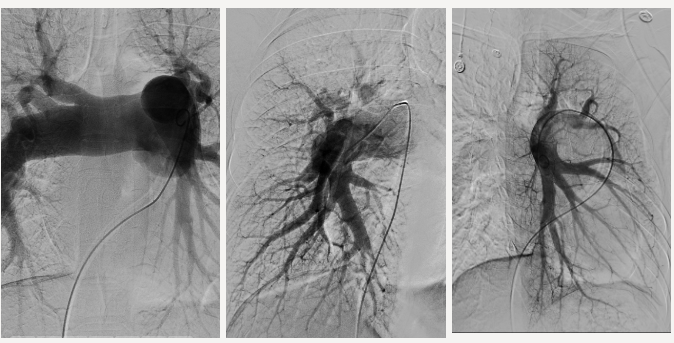

经过心脏彩超和肺动脉造影检查发现

阿珍竟然是

先天性心脏病——房间隔缺损

右心增大

肺动脉重度高压

通过左房肺静脉CTA检查

张琳发现

阿珍的肺动脉高压

是先心病引起的

房间隔缺损导致

肺静脉异位引流

就是本该回到左心房的肺静脉血液

一部分汇入到了上腔静脉